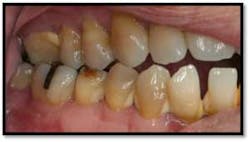

UL/LL reflected in a mirror and UL/LL radiograph

Tissue is light pink, tight and firm. All pockets are 1-3mm, no BOP

LR lingual post Tx and LL lingual post

Tissue is light pink, tight and firm. Pockets 1-3mm no BOP